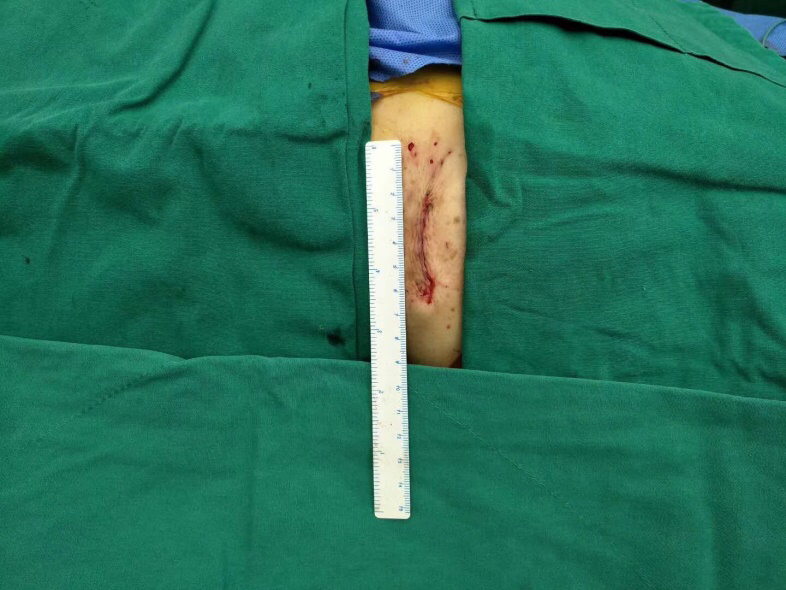

图片说明:胸前4厘米的手术切口。

整个手术过程非常顺利,仅耗1个半小时,胸骨肋骨无任何破坏,也无需体外循环,出血量未超过100ml。术后2小时老太太完全清醒过来并拔除气管插管,还能与医务人员轻松交谈。